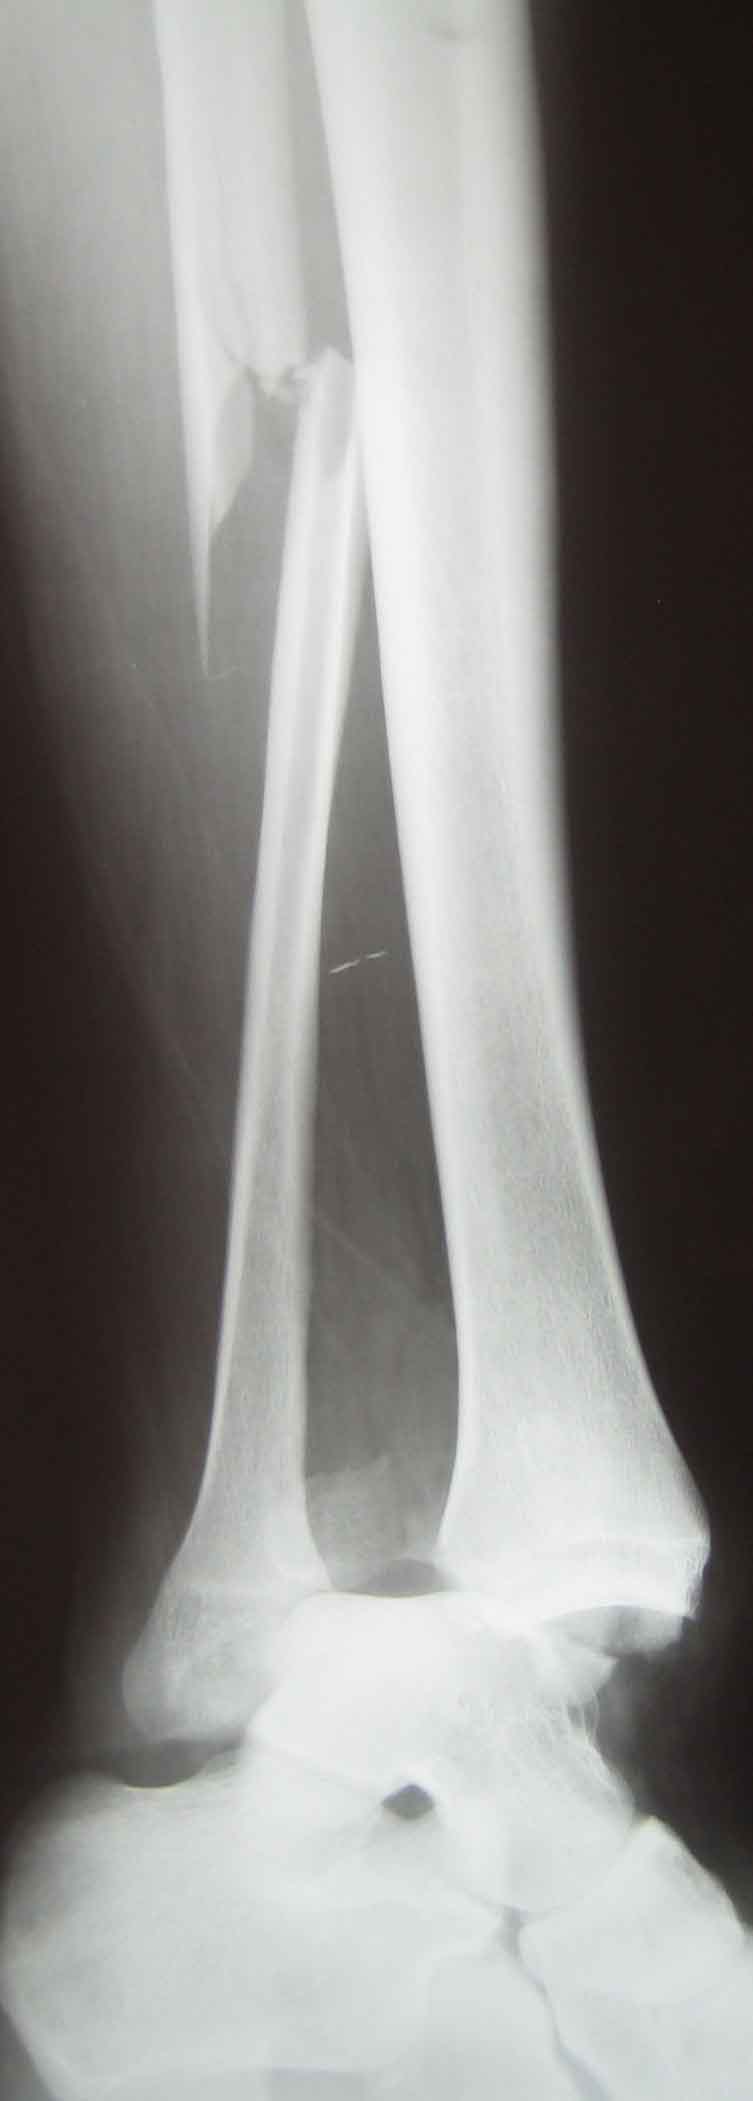

Д-з: закрытый переломо-вывих правого голеностопного сустава, перелом

Травма тяжелая, ожидаем большой отек вскоре. Что сделать - сильно зависит от возможностей учреждения, и при поступлении. Можно и закрыто вправить, наложив гипс, или положить на вытяжение, а загипсовать по спадении отека. Можно вправить и фиксировать аппаратом временно или окончательно, а можно вправить и ввести под ЭОП несколько винтов через проколы.

Надсиндесмозная травма с разрывом не только межберцового синдесмоза, но и межкостной мембраны на большом протяжении. По-этому ( кожа и ex-fix, повторяться не буду, фиксация малоберцовой открыто или минидоступом-по желанию хирурга), но я бы провел ДВА позиционных винта (кортикальных 3,5 мм) и через четыре кортикала.

Povrezdenije tipa "Maisonneuve" . Otsen plohoje . Kak vise kollega pisal povrezden ne tolko sindesmos no i mezkostnaja membrana . V dobavok ko vsemu povrezdenija v oblasti golenostopa vsegda VNUTRISUSTAVNIJE ! Po etomu vosstanovlenije anatomii vazno . I zakritije manipulatsii s malobertsovoi v etom slutsaje , na moi vzgljad, ne dopustimi .